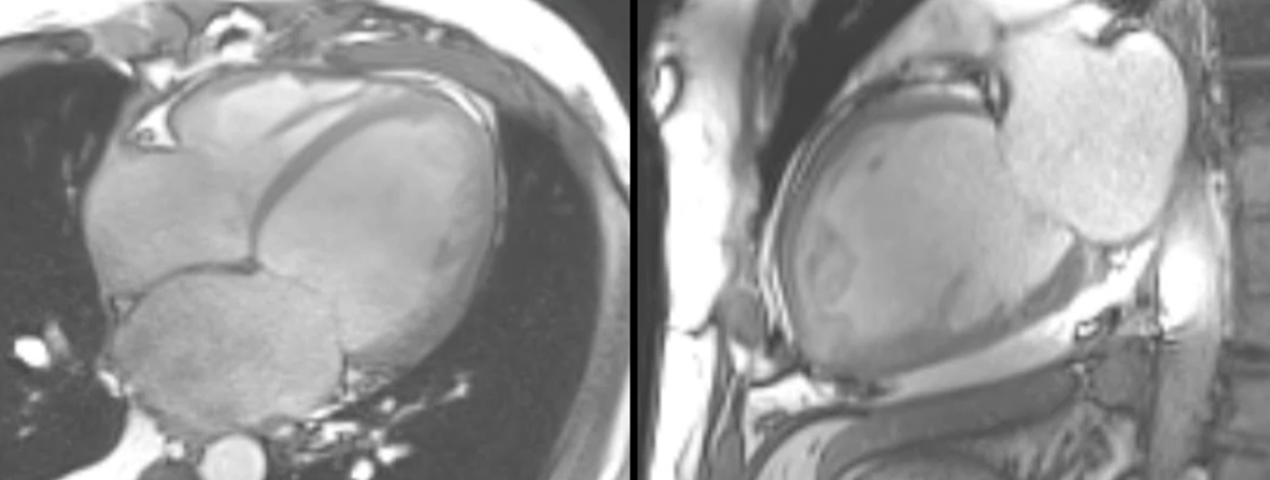

Case 114: "Ring-Like" Enhancement

"Ring-like" enhancement lowers the threshold for genetic testing in patients with dilated cardiomyopathy.

This pattern of enhancement has started receiving some attention because of its association with both inflammatory and genetic conditions, in patients with dilated cardiomyopathy.